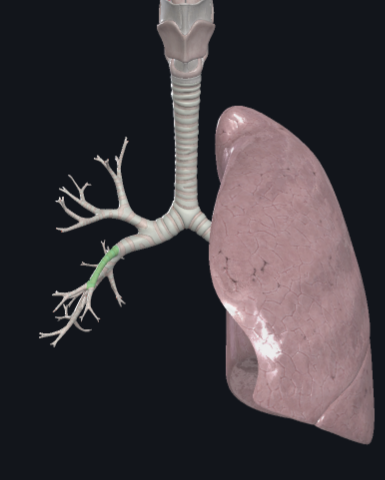

What structure is this?

Right main bronchus

What structure is this?

Right superior lobar bronchus

What structure is this?

Middle Lobar bronchus

What structure is this?

Right inferior lobar bronchus

What structure is this?

Left main bronchus

What structure is this?

Left superior lobar bronchus

What structure is this?

Left inferior lobar bronchus

What structure is this?

The carina